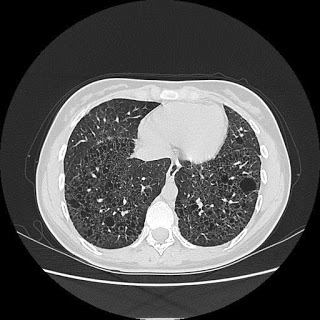

وجدان ، فتاة من الدار البيضاء تبلغ من العمر 26 عامًا ، متزوجة وأم لطفل يبلغ من العمر 4 سنوات ، عانت منذ ولادتها من تليف رئوي مجهول الأسباب.

بسبب فشل الجهاز التنفسي ونقص الأكسجين ، غالبًا ما تحتاج وجدان إلى حصص علاجية بالمستشفى والتي عادة ما تكون مكلفة لها ولأسرتها الصغيرة بسبب حالتها الحرجة ، فكان لزاما أن تبدأ تكتفي بالأوكسجين ، من أجل تسهيل تنفسها ، وبفضل تبرعات قليلة ، تمكنت من الحصول على مُكثّف أوكسجين ، والذي غالبًا ما تستخدمه في المنزل ، إذا أرادت البقاء على قيد الحياة …

إلى متى ستتواصل معاناة وجدان ؟ سؤال يبقى جوابه رهينا بزرع رئة ، هذا ما أخبرها طبيبها : زرع الرئة هو الأمل الوحيد الذي يمكن أن يطيل عمرها …